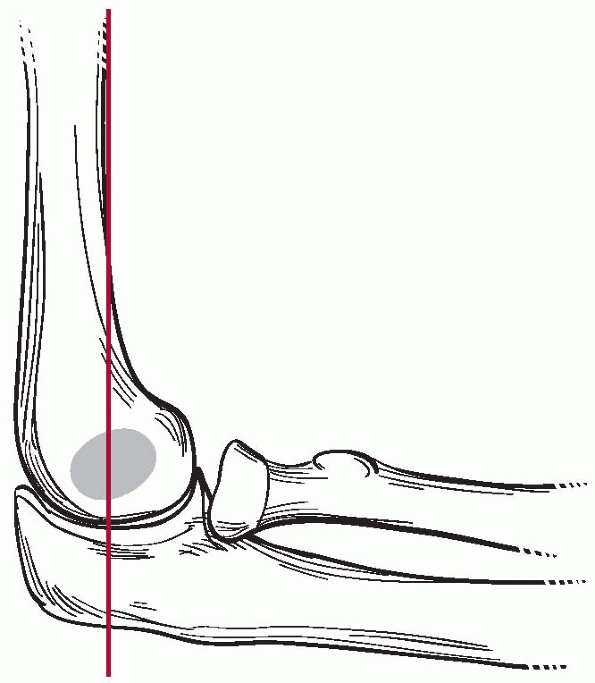

for the presence of a supracondylar fracture. The anterior humeral line

should cross the capitellum through the middle third on a true lateral

of the elbow (Fig. 14-14). In an extension-type

supracondylar fracture, the capitellum is posterior to this line. The

Baumann angle, also referred to as the humeral capitellar angle, is the

angle between the long axis of the humeral shaft and the physeal line

of the lateral condyle (normal range, about

9 to 26 degrees) (Fig. 14-15). A rule of thumb is that a Baumann angle of at least 10 degrees is acceptable; a decrease in the Baumann angle is a sign that a fracture is in varus angulation.